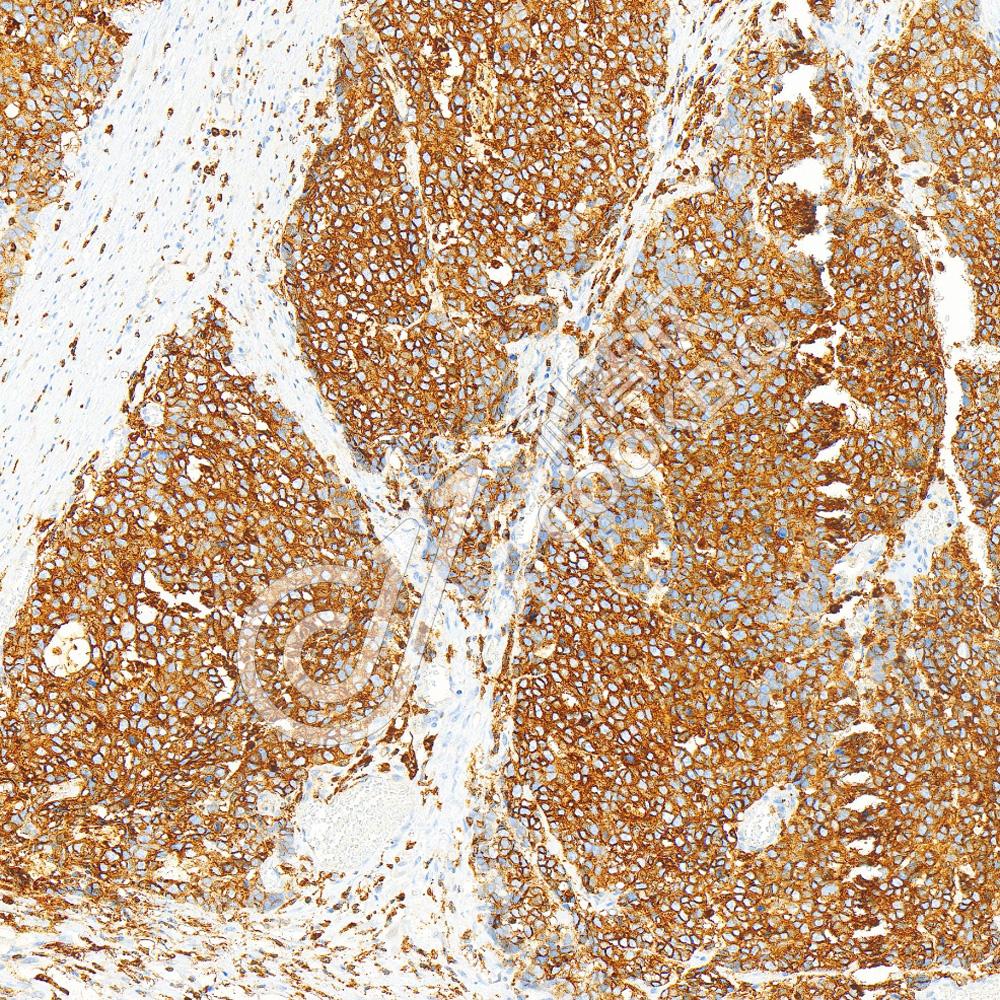

IHC检测p63蛋白(货号 K5450195).

样品: 人扁桃体, 4%多聚甲醛 (货号KSG1101) 固定12-24小时.

抗原修复: 柠檬酸抗原修复液(干粉, pH 6.0) (KSG1201), 高压锅均匀喷气计时2分钟.

—抗: 1: 4500稀释, 4℃ 孵育过夜.

二抗: S-vision免疫组化多聚二抗(山羊抗兔),即用型 (货号KB3906), 室温孵育20分钟.